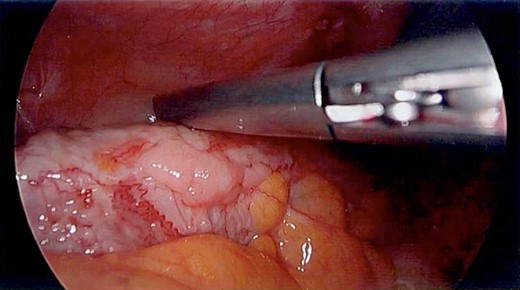

Unfortunately, the patient presented with a large bowel obstruction two weeks after starting chemotherapy. At laparotomy, the point of obstruction was found at the proximal ascending colon, with macroscopic evidence of circumferential mural thickening with a white lathered appearance of the entire right colon (Figs 5 and 6). Peritoneal and patchy omental disease were also observed (Figs 7 and 8)—an omental biopsy was taken which later confirmed an ovarian primary. The decision was made to proceed with a relatively low-risk procedure given that the patient was actively immunosuppressed and had become quite frail; she was therefore defunctioned with a loop ileostomy. The priority was for the patient to be able to continue her neoadjuvant chemotherapy from a survival benefit perspective; the risks of delaying treatment by performing a more extensive resection with its attendant potential complications was not deemed to be in her best interests. A Foley catheter was passed beyond the ileo-caecal valve for decompression. The patient had an uncomplicated recovery postoperatively and was able to complete the scheduled 3-month course of chemotherapy.

The white leathery appearance of large bowel is a rare finding, and has not been described in relation to linitis plastica of the colon, but if observed in a diagnostic laparoscopy should prompt further investigation as it may represent underlying diffuse disease and potential for large bowel obstruction.